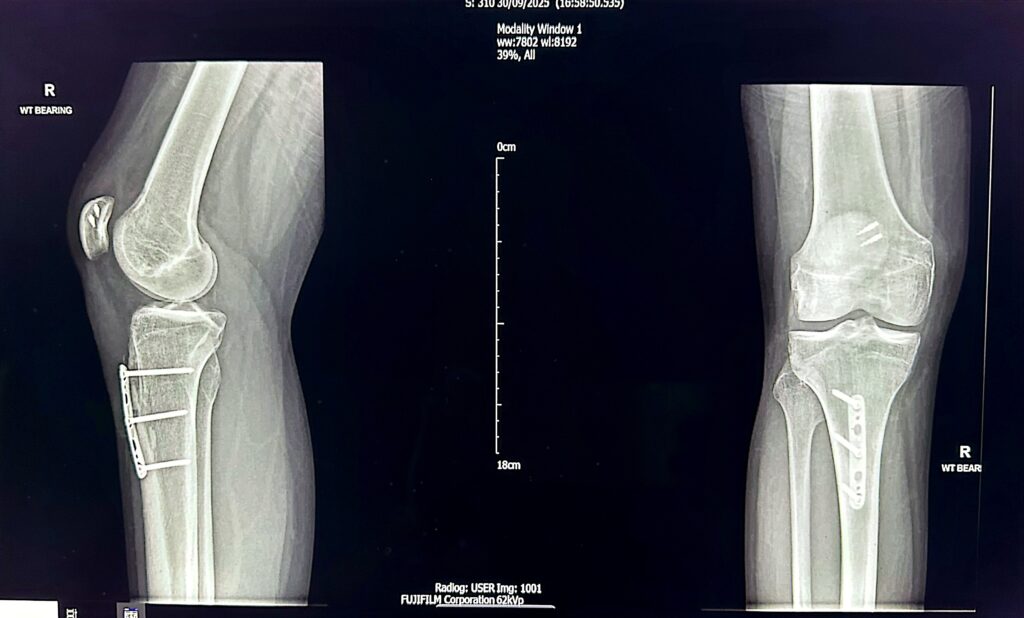

MPFL reconstruction is often combined with tibial tubercle osteotomy depending on the presenting pathology. This procedure involves the surgical movement of the tibial tuberosity (the area on the shin bone where the patellar tendon attaches) either medially (inwards) or inferiorly or both depending on the risk factors present. The fixation is held with a plate /3-4 screws to hold the repositioned new bone in its new position. It takes 3-4 months for the bones to heal completely.

Below is the X-ray of a young person who has undergone MPFL+TTO surgery 6 months ago, the osteotomy site in tibia has completely healed.